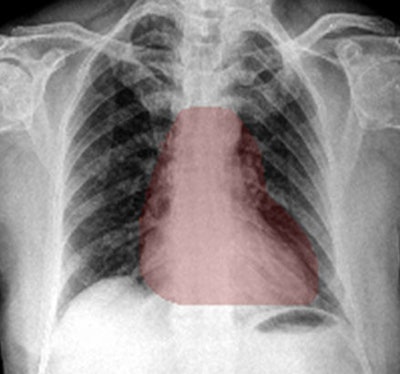

The algorithm can generate heat maps using two methods: occlusion visualization and integrated gradients. The occlusion visualization technique color codes an image patch that is considered to be the most significant abnormality on the image, while the integrated gradients method accounts for the sensitivity of each pixel prediction and obtains an approximate attribution score for each pixel.

Heat maps generated by chest x-ray AI software. The occlusion-visualization heat map method (above) color codes the image patch that is considered to be the most significant abnormality on the image. The integrated gradients heat map method (below) accounts for the sensitivity of each pixel for predicting an abnormality and obtains an approximate attribution score for each pixel. It then generates a sensitivity heat map. Images courtesy of Dr. Shalini Govil.These heat maps can help win over doctors who may be skeptical about the benefits of deep learning and AI, according to Govil.